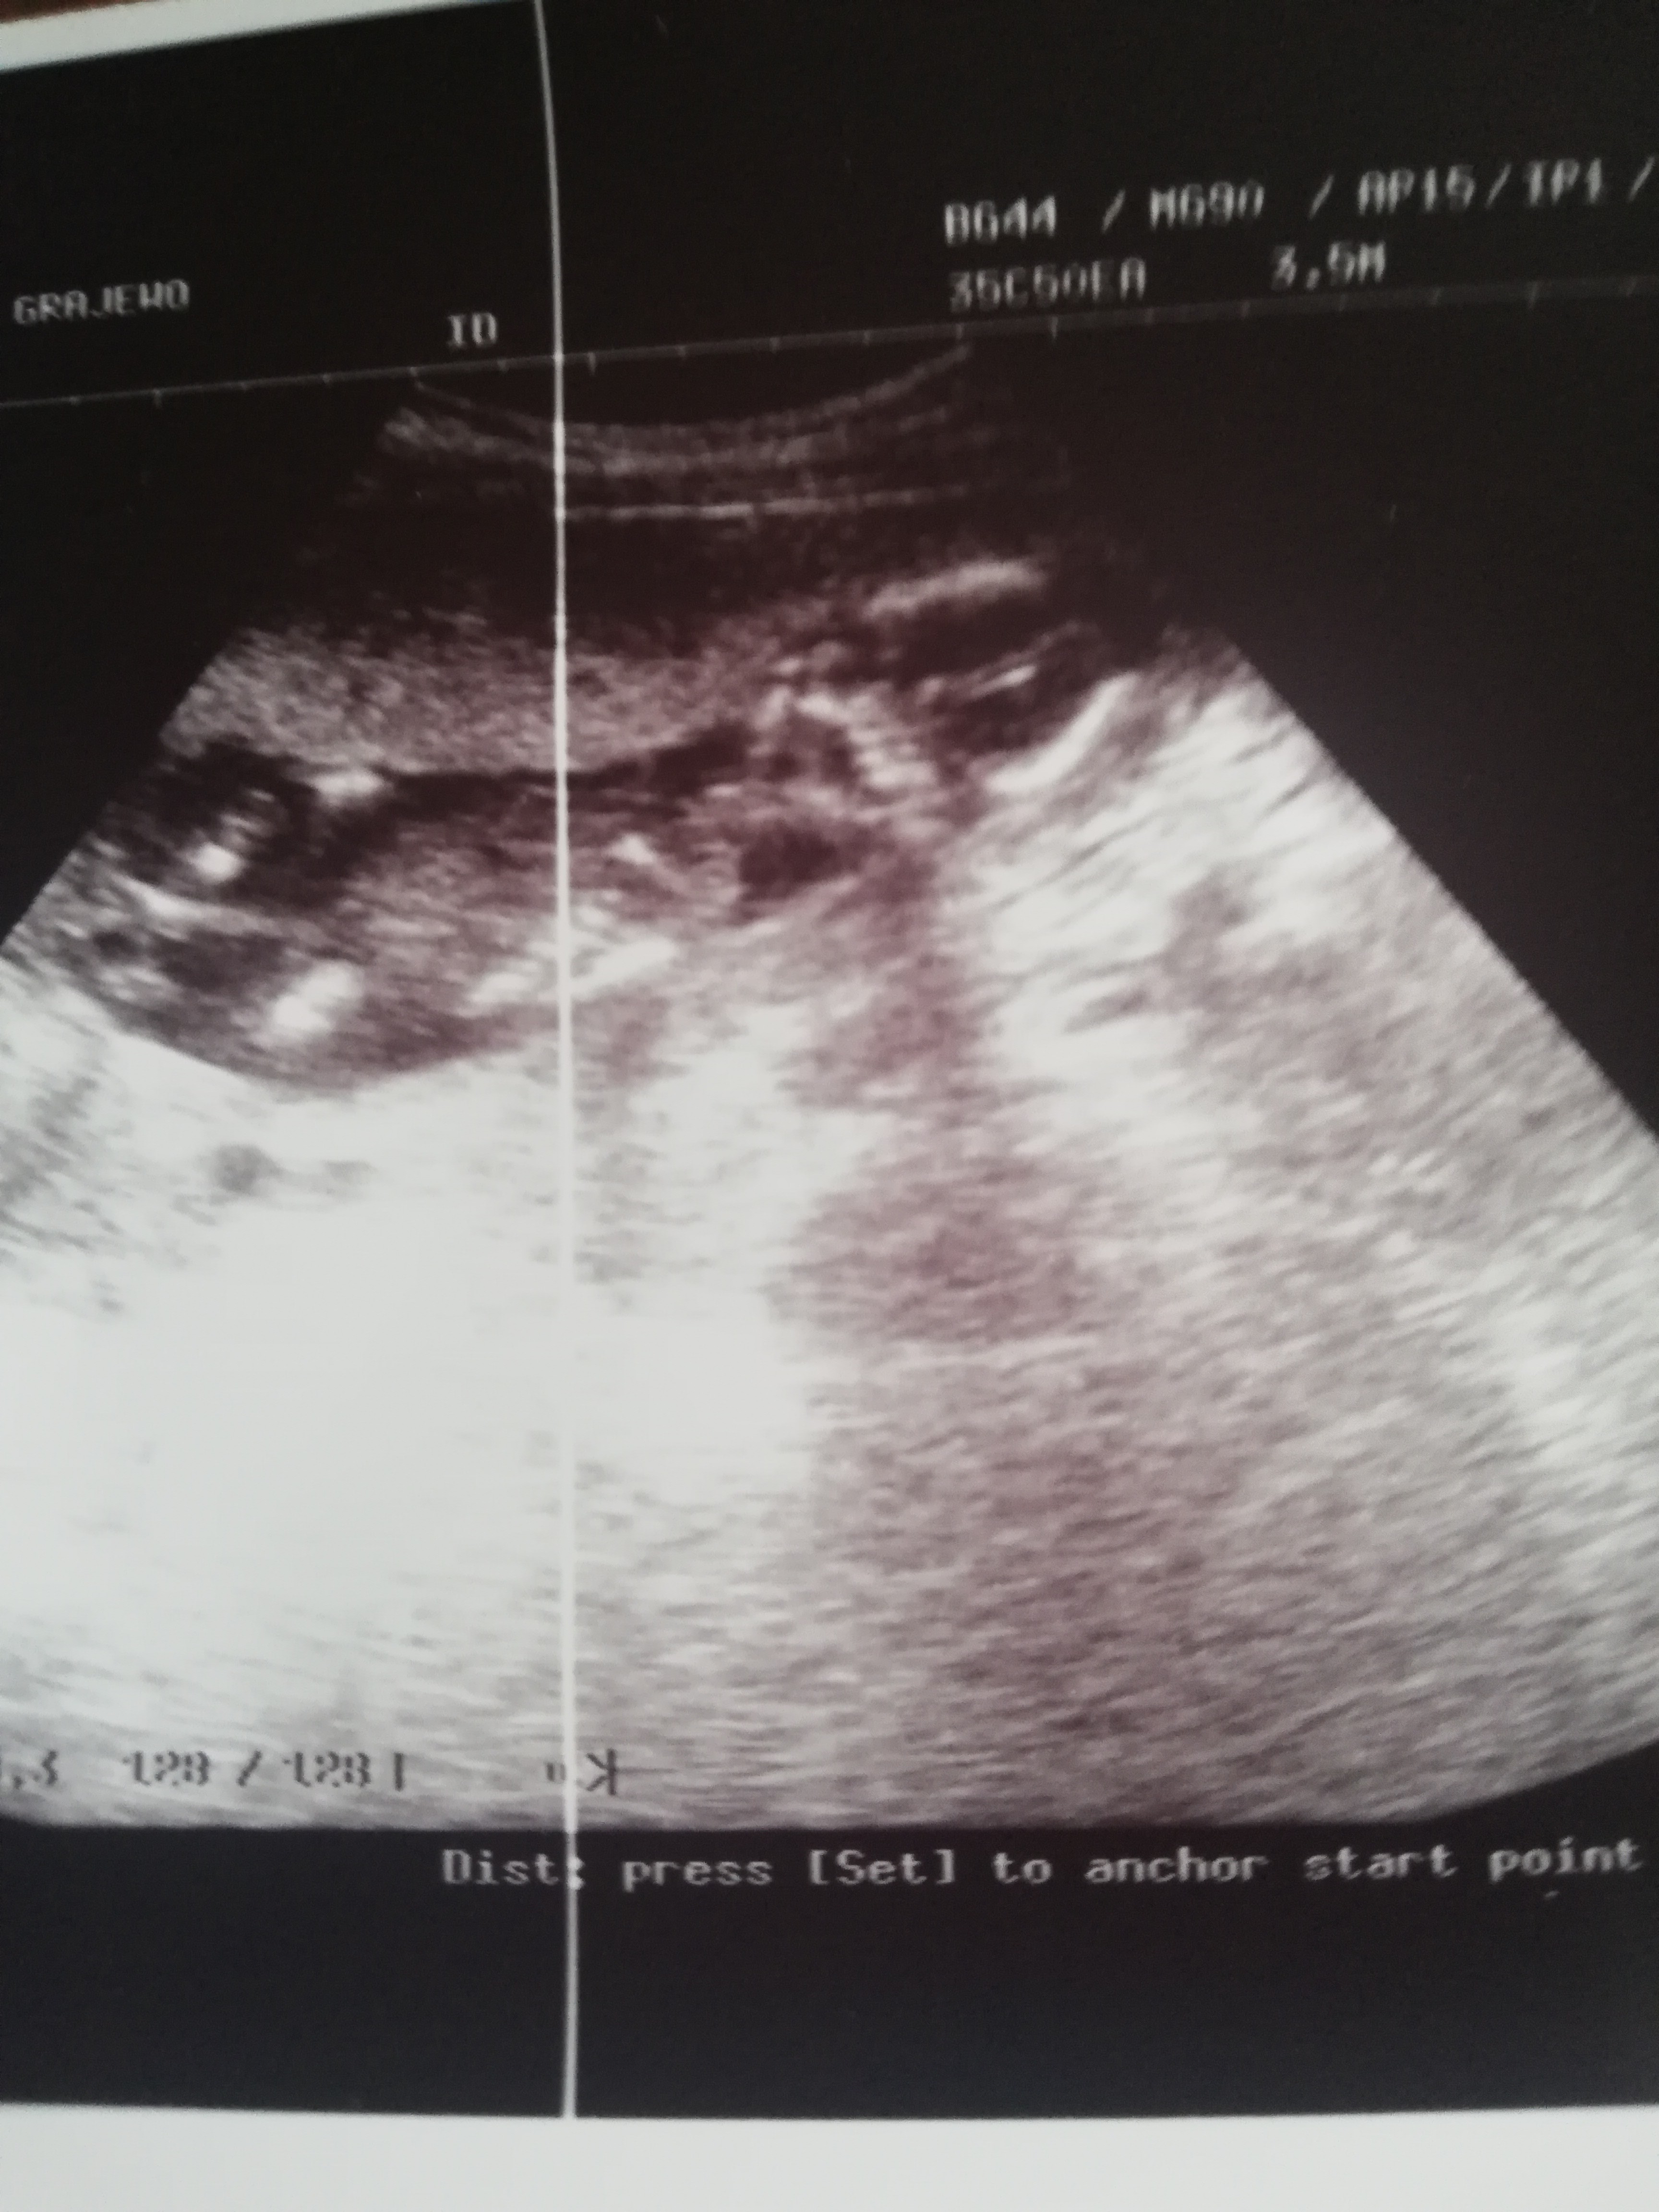

Dziewczyny na wasze oko jaka to płeć? Zdj zrobione w 15 tyg ciąży. W 11 tyg moja ginekolog stwierdziła że wygląda jej na chłopaka a na badaniu prenatalnym inna doktor stwierdziła nie przekonująco że to dziewczynka najprawdopodobniej. Wiem że zdrowie najważniejsze jednak jestem ciekawa waszych opinii